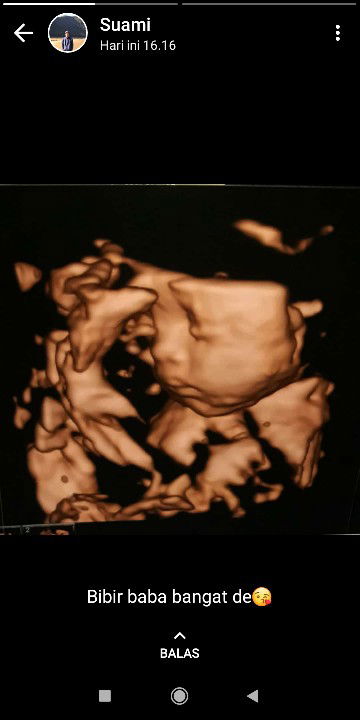

calon ibu anak 1